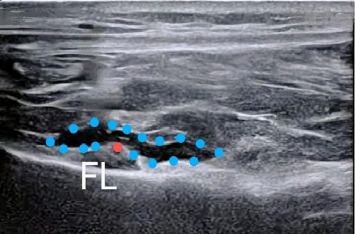

Abstract Image